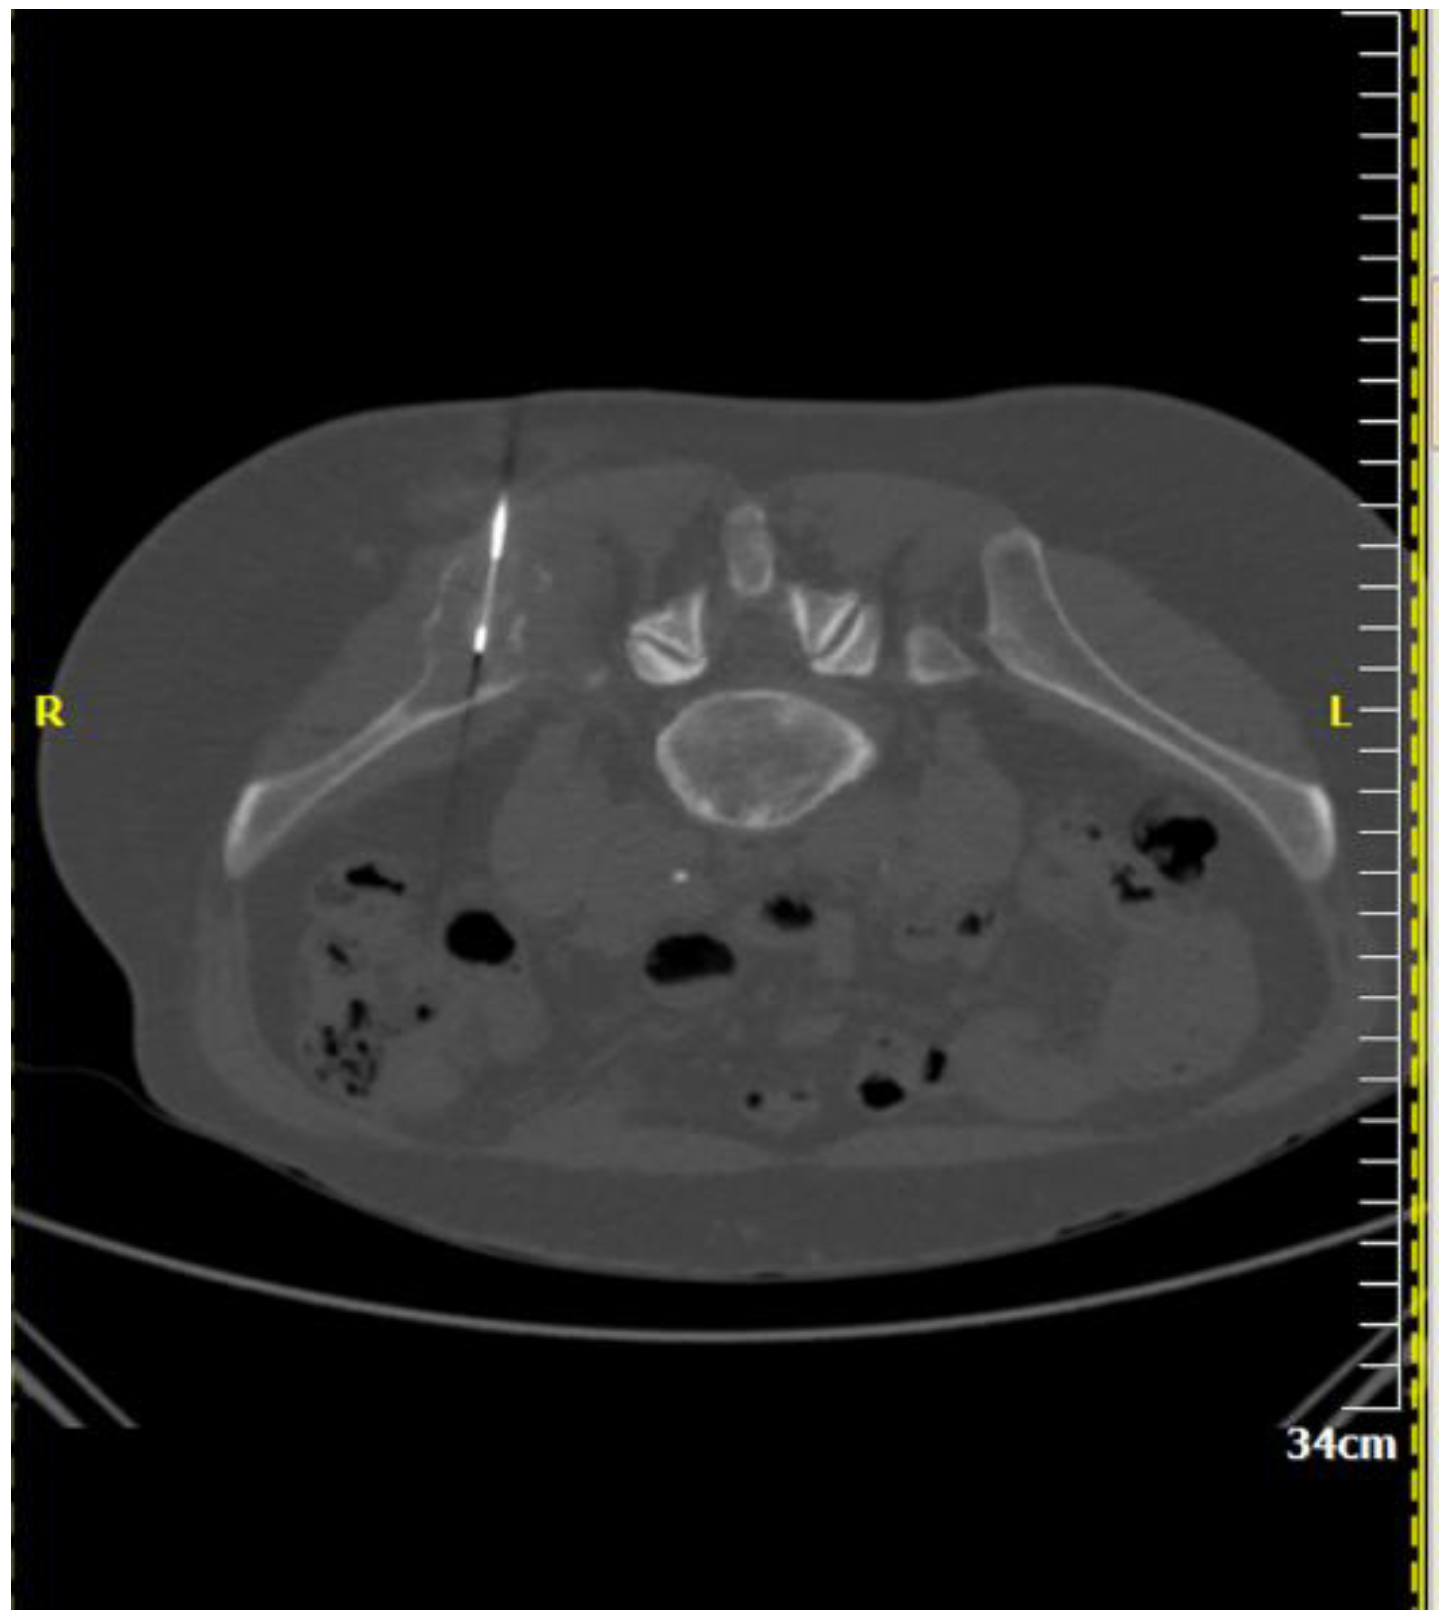

Figure 2.

A 64-year-old male patient with multiple osteolytic lesions. Computed tomography axial scan: there is a lytic lesion in the right iliac bone. The result of percutaneous, imaging-guided biopsy was metastasis from small cell bronchogenic carcinoma.